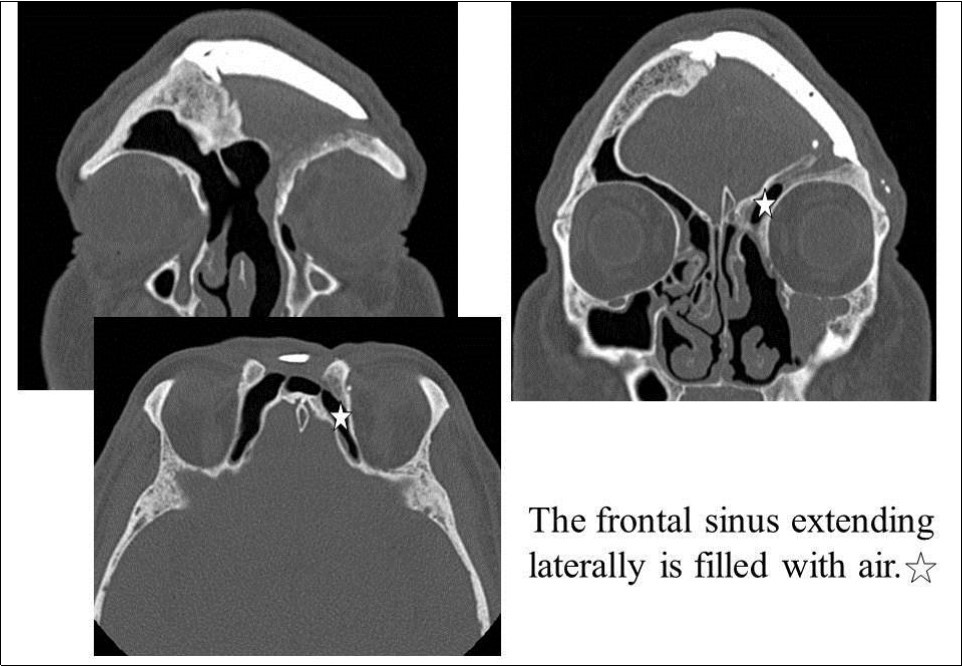

Recurrent frontal sinusitis was suspected, and the patient was referred to our department for evaluation on February 14, 2007. On initial evaluation, the left upper eyelid swelling was resolved; however, paranasal sinus computed tomography (CT) showed two left frontal sinus cysts (Figure 1). The patient had a history of hypertension that was well-controlled on oral medications. No other major disorders were present, including diabetes or heart disease.

Figure 1.CT of the paranasal sinuses showed two left frontal sinus cysts. Black arrows: ceramic implant. Black stars: two left frontal sinus cysts

On April 16, 2008, reoperation was performed to place a ceramic implant, but some pus was found in the left lateral sinus. The lesion was debrided, the dead space was filled with muscle, and surgery was completed without ceramic implantation. On October 17, 2008, another surgery confirmed that the frontal sinus was clean, and a ceramic implant was placed. The postoperative course has been good, and as of May 2009, the frontal sinus extending laterally is filled with air (Figure 5, Figure 6).

Figure 5.Paranasal sinus CT after the last surgery. White star: The frontal sinus extending laterally is filled with air.